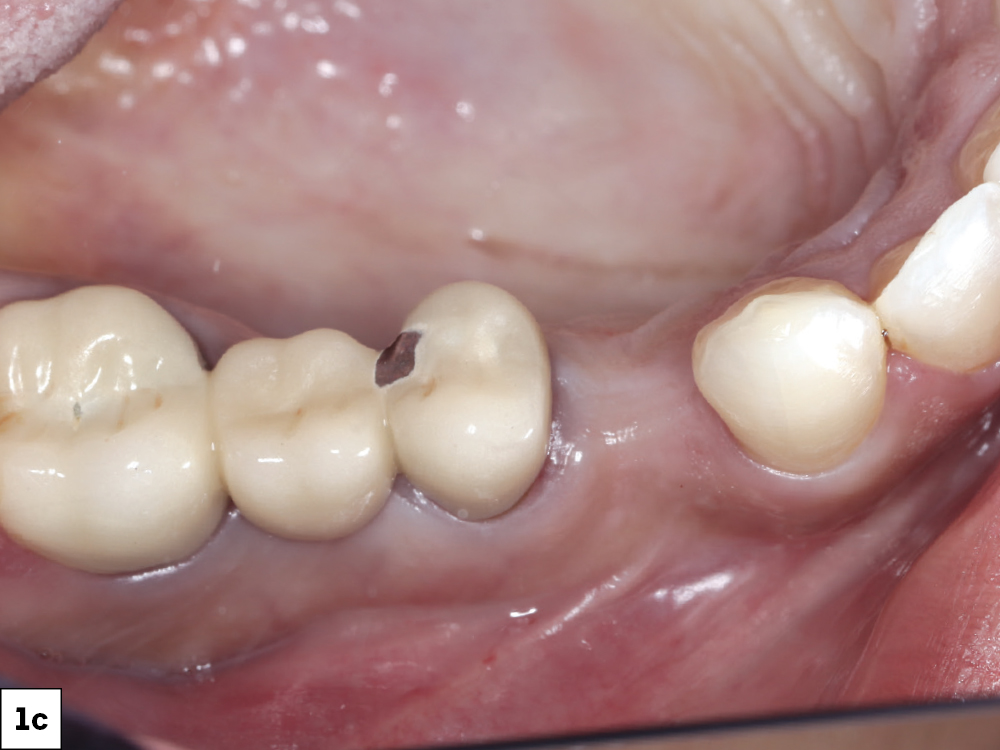

At the one-week follow up, both implants demonstrated excellent integration with healthy peri-implant tissues and no inflammation-a

At the one-week follow up, both implants demonstrated excellent integration with healthy peri-implant tissues and no inflammation-b

At eight weeks, mature keratinized mucosa framed the zirconia crowns with stable crestal bone levels and ideal emergence profiles were confirmed radiographically-c

At eight weeks, mature keratinized mucosa framed the zirconia crowns with stable crestal bone levels and ideal emergence profiles were confirmed radiographically-d

Figures 13a–13d: At the one-week follow up, both implants demonstrated excellent integration with healthy peri-implant tissues and no inflammation. At eight weeks, mature keratinized mucosa framed the zirconia crowns with stable crestal bone levels and ideal emergence profiles were confirmed radiographically.